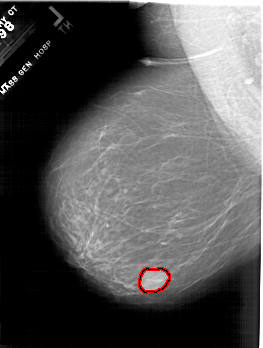

A_1801_1.RIGHT_MLO

LEFT_MLO LINES 6601 PIXELS_PER_LINE 4981 BITS_PER_PIXEL 12 RESOLUTION 43.5 OVERLAY